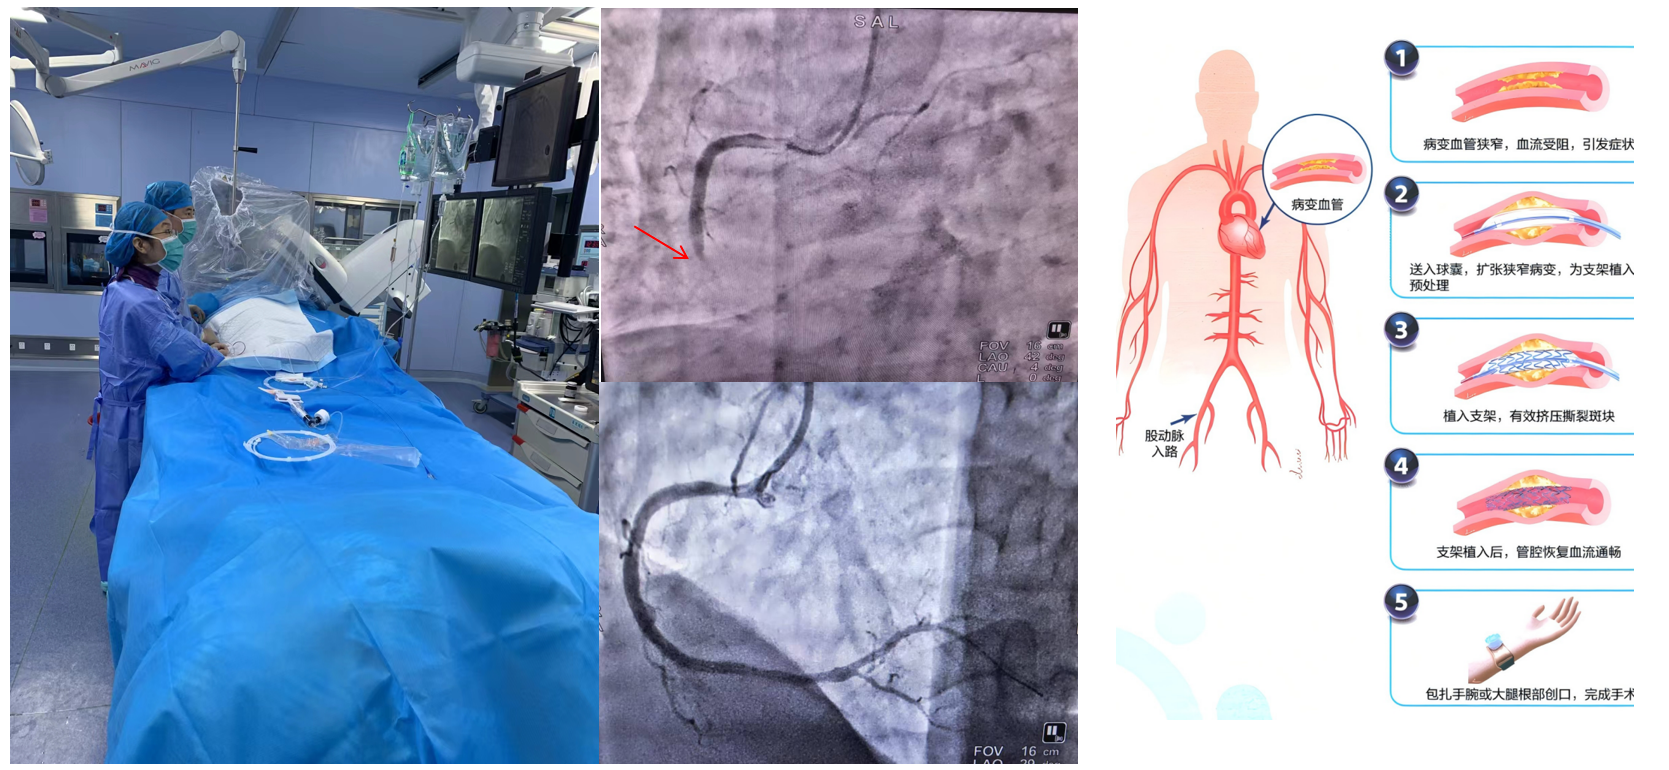

基本情況:重慶醫科大學附屬璧山醫院(重慶市璧山區人民醫院)心血管內科成立于1995年,是集醫療、教學、科研為一體,涵蓋高血壓、冠心病、心力衰竭、心律失常、老年瓣膜性心臟病、動脈硬化等疾病診療及心臟康復的專業學科。科室擁有普通病房和監護病房CCU)、獨立心導管室及心功能室,心血管病專科門診年收治病人5000+人次。常規開展經皮冠狀動脈介入診療(包括IVUS、OCT及FFR指導下的左主干、分叉、鈣化及慢性閉塞等復雜病變的介入治療)、心律失常導管消融(房顫、房撲、陣發性室上性心動過速、早搏、室速等射頻、冷凍、脈沖電場消融)、起搏器植入(單/雙腔起搏器、無導線起搏器、植入型心臟轉復除顫器、心臟再同步化治療)、左心室造影、右心導管、肺動脈造影及球囊擴張術、左心耳封堵術、心臟瓣膜病介入治療(經導管主動脈瓣置換術)、先心病介入封堵術等,年介入量2500

設施設備:科室擁有GE Innova IGS 5數字減影血管造影機1套、美國強生CARTO?三維心臟電生理成像和導航系統1套、美國箭牌Autocat2主動脈內球囊反搏泵1套、成都錦江LEAD-7000心臟多道電生理記錄儀1臺、成都錦江VATION-100C心臟射頻消融儀1臺、成都錦江VATION—CooIPumP灌注泵1臺、美國飛利浦偉康V200有創呼吸機1臺、美國飛利浦偉康V60無創呼吸機10余臺、美國Mortara X-Scribe II運動負荷測試系統1套、上海光大ECG-6951E心電圖機3臺、深圳理邦SE-1201數字式十二道心電圖機2臺、匯醫融工CVFD-II(F)心血管系統狀態監測儀1臺、哈特凱爾FQ-17心衰超濾脫水裝置1臺、日本光電除顫儀3臺、六分鐘步行監測評估系統1臺、臨時起搏器3臺、動態心電圖記錄器30余臺、動態血壓記錄儀30余臺、心電監護儀47臺。這些先進設備的引入與應用,極大地提高了疾病的診斷準確率與治療效果,為科室醫療技術水平的提升提供了強有力的硬件支撐。5ddb6e0a2b204e23a5a95036a804075d.Png

科室榮譽:科室已成功創建國家級胸痛中心(標準版)、國家級心衰中心、國家級高血壓達標中心、國家級房顫中心,獲批“重慶市臨床重點專科”、“重慶市公共衛生重點專科”、“重慶市疑難高血壓聯盟單位”、“西部心臟介入護理專科聯盟單位”“市級公立醫院黨建示范黨支部”、“重慶市璧山區冠脈介入、心律失常質量控制中心”,重慶醫科大學臨床醫學碩士學位授予點等。